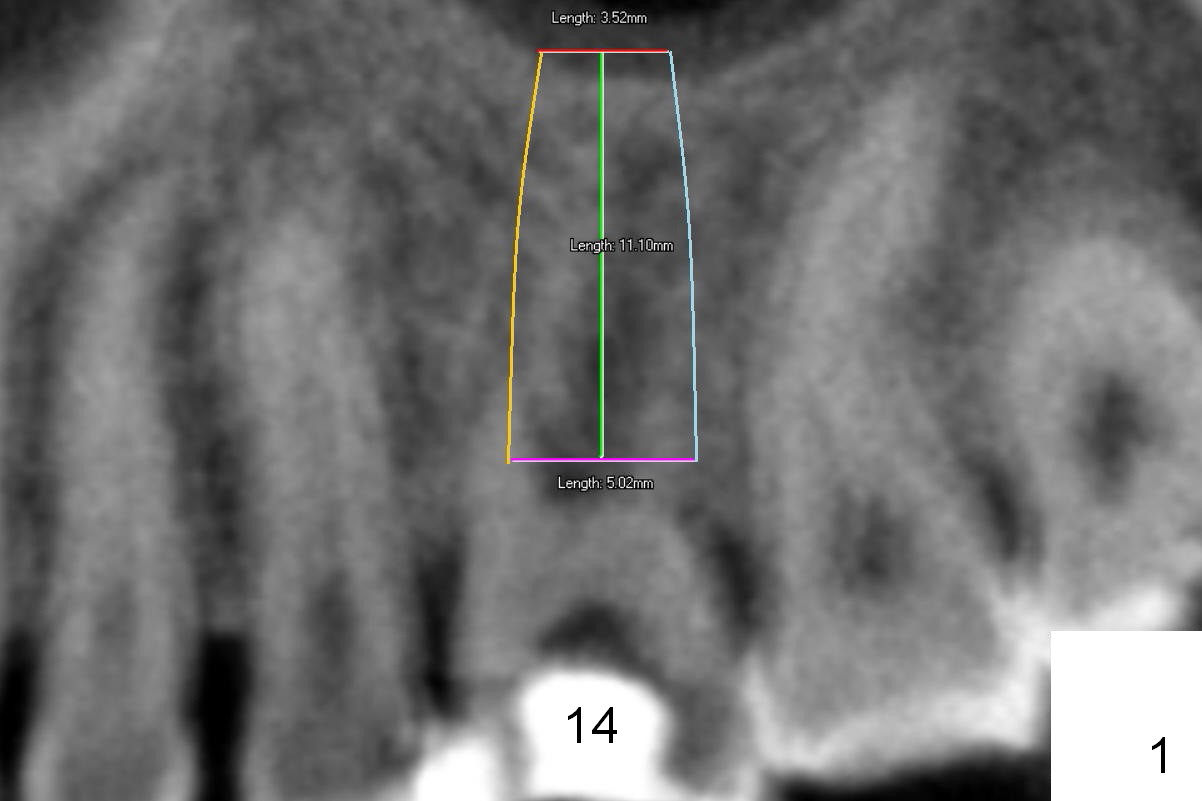

Preop CT shows that the septum appears to be able to hold a 11 mm long implant (Fig.1 sagittal section). There are periapical radiolucent lesions of the buccal (Fig.2 (coronal section) B) and palatal roots; bone height above the buccal apex is ~ 2 mm (Fig.3). When the tooth #14 is extracted, a 1.6 mm pilot drill is used to start osteotomy in the middle of the fairly thin septum (Fig.3 red line, Fig.4 S). It is hoped that Magic Expanders (ME) can enlarge the osteotomy by pushing the buccal and palatal bone plates of the septum outward (Fig.5 arrows).

It seems that the provisional traps food. The former has been removed by the patient by the time she returns 3.5 months postop. The gingiva around the implant is healthy. The organization of the bone graft has changed (Fig.13, as compared to Fig.8,9). The implant has osteointegrated. Take photos to show the buccal and palatal gingival margin before impression. In fact the newly formed gingiva covers the margin of the abutment 5 months postop (Fig.14). Laser gingivectomy is performed prior to impression. Provisional should be kept in place with good oral hygiene. The crown dislodges 8 months post cementation, probably due to bruxism, small, short abutment and open margin (Fig.15 (taken after recementation; the residual cement is removed later)).